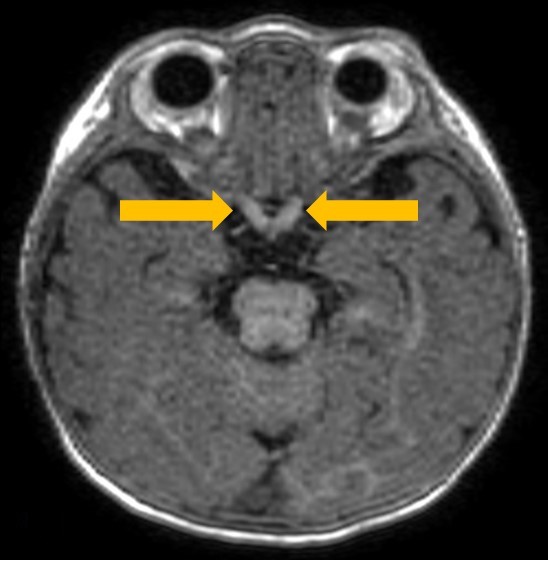

A 5-month-old boy presented with decreased oral intake and poor urine output. On admission, he was hypertonic and irritable. The boy’s parents reported worsening irritability since birth, poor weight gain...

11/09/2020